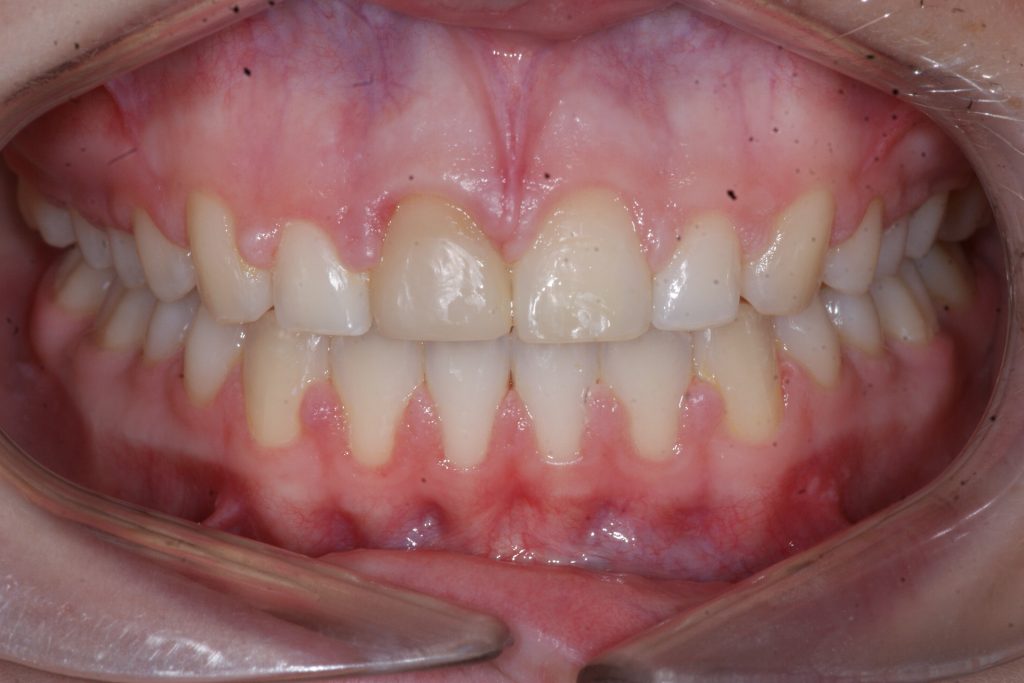

Correction d’une malocclusion de type Classe II division 1 avec excès d’espace aux 2 arcades.  Des appareils fixes (boîtiers) et une expansion palatine furent nécessaires pour améliorer ce sourire.  Traitement chez une adolescente, réalisé en 26 mois.